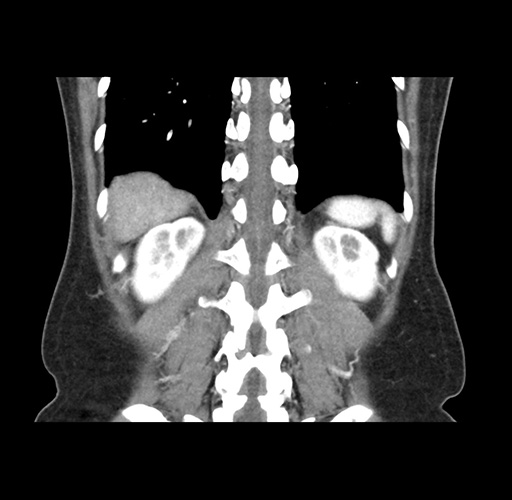

Imaging Analysis

Look through the patient's CT scan to identify any areas of concern for the necessary procedure.

Based on your CT findings, which issue(s) would give reason for "planned slowing down moment(s)" in this case?

Considering a standard left lateral sectionectomy procedure, what step(s) of the operation would you do differently in this case ?